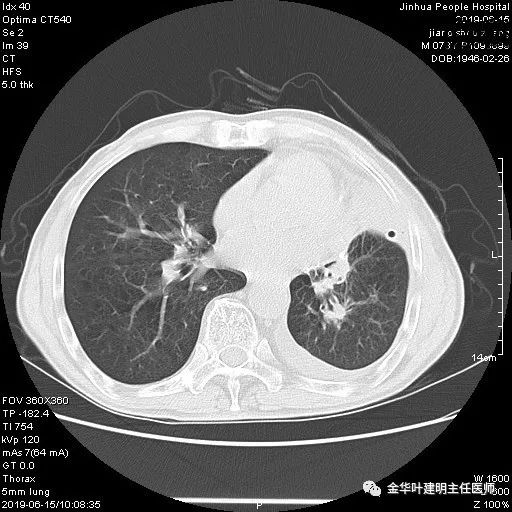

6.15上午:24小时胸管引流出血性液250ml;复查胸部CT示: